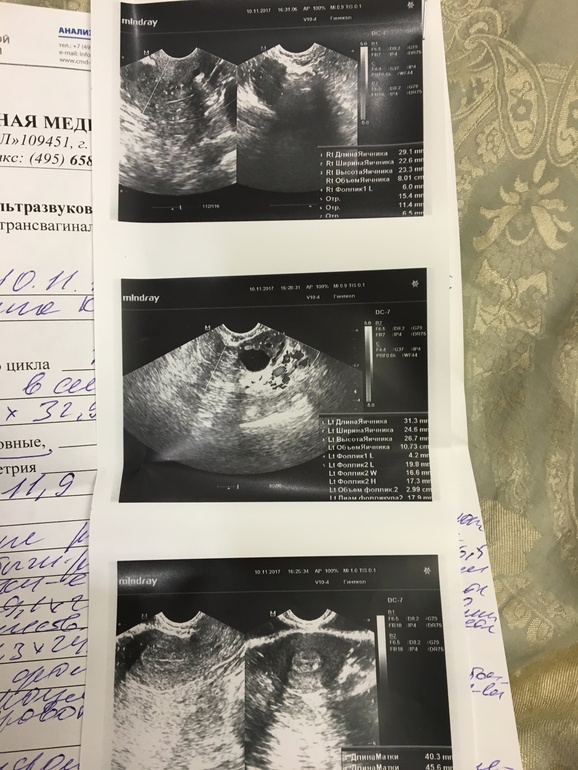

Девочки посмотрите на УЗИ, что скажете, шансы есть что беременность могла на ступить? Что о эндометрии скажете?

Какая беременность то на 12 день цикла? Овуляция только планируется. В заключение так и написано. Что спрашивать!?